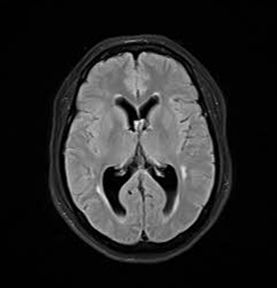

An Occipital Headache as the First Presentation of Multiple Third, Fourth, and Lateral Ventricular Cavernous Malformations: A Case Report and Review of Literature

Background: Cavernous hemangiomas are common benign vascular malformations. Their existence in the intraventricular region is very rare. Case Reports: A 43-year old woman with an occipital headache was admitted to the emergency ward. Brain computed tomography scan showed mild hydrocephalus and multiple intraventricular isodense lesions. Imaging findings, especially of Gradient Resonance Echo imaging, were in favor of multiple intraventricular cavernous malformations. Conclusion: This is a rare presentation of multiple cavernous malformation as occipital headache without needing surgical intervention in this phase. Coexistence of periventricular plaques like Radiologically isolated syndrome of Multiple sclerosis is another unique aspect in this report. [GMJ.2017;6(1):61-65]